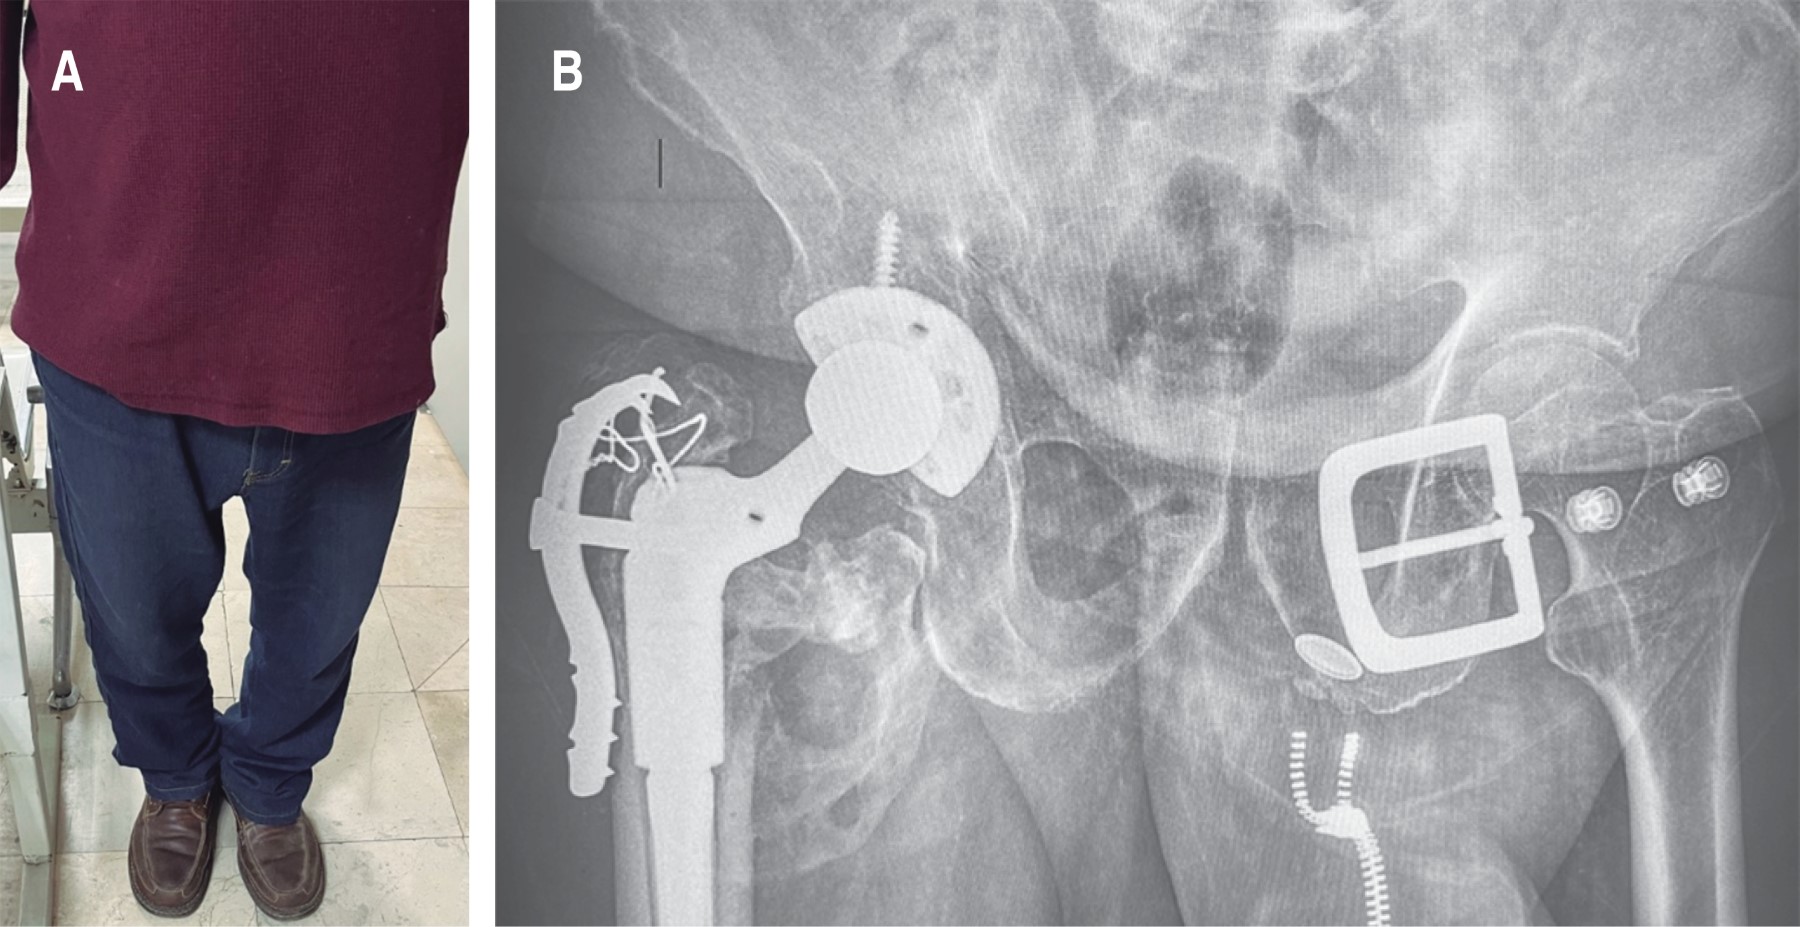

Hombre de 79 años de edad, jubilado. Quien no tiene antecedentes personales de interés para el caso clínico, solamente hernia inguinal indirecta derecha de años de evolución, no cuenta con antecedentes ortopédicos, tabaquismo positivo, niega toxicomanías y alcoholismo. El paciente refiere que, mientras caminaba por superficie irregular en una sierra, sufre caída de su propia altura posterior a "pisar mal", cayendo con un mecanismo de hiperflexión de la cadera derecha realizando un "split", con lo que presenta de forma súbita incapacidad para reincorporarse, coxalgia derecha y posición distinta de miembro pélvico derecho al contralateral, incapaz de movilizar. A su llegada a urgencias, tras exploración física dirigida, extremidad pélvica derecha con importante acortamiento y rotación externa. Estudios de gabinete: se solicita proyección radiográfica (Figura 1A); por la complejidad del trazo, se decide solicitar tomografía axial computada para definir mejor la fractura (Figura 1B).

Figura 1